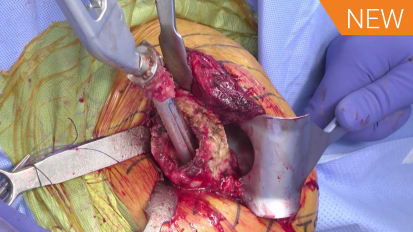

On behalf of SDSI Society Meeting George Athwal, MD discusses what's new with the B2 looking at classification, anatomy, and augmented implants.